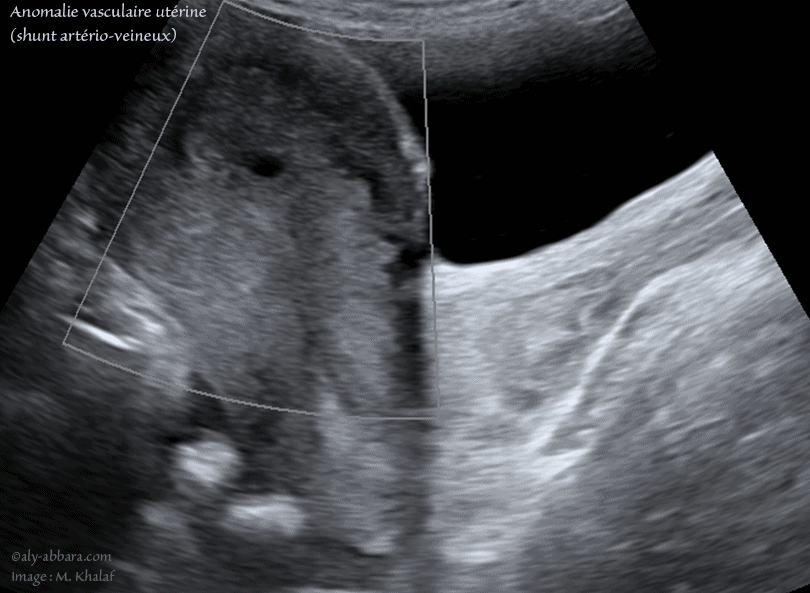

• Anomalie vasculaire utérine de type " shunt artério-veineux ou pseudo anévrysme " d'origine traumatique (accidentel) :

• Ce shunt vasculaire au sein du myomètre de la paroi utérine antérieure est survenu chez une femme âgée de 31 ans, consultant, au service des urgences gynécologiques pour douleur pelviennes est métrorragies importantes, une semaine après une hystéroscopie opératoire et résection d'une rétention placentaire, suite à un accouchement ayant lieu deux mois auparavant.

• L'échographie met en évidence la présence, au sein de la paroi antérieure de l'utérus, d'une lacune hypoéchogène à contour irrégulier. Le Doppler couleur montre qu'il s'agit d'une pathologie vasculaire débutant dans la cavité utérine et traversant verticalement les deux tiers de l'épaisseur myométriale profonde et antérieure.

L'analyse du spectre-Doppler est en faveur de flux artériels tourbillonnants et se connectant à la circulation veineux située dans la couche superficielle du myomètre.

• Le diagnostic retenu celui de shunt artério-veineux accidentel, ou un faux anévrysme.